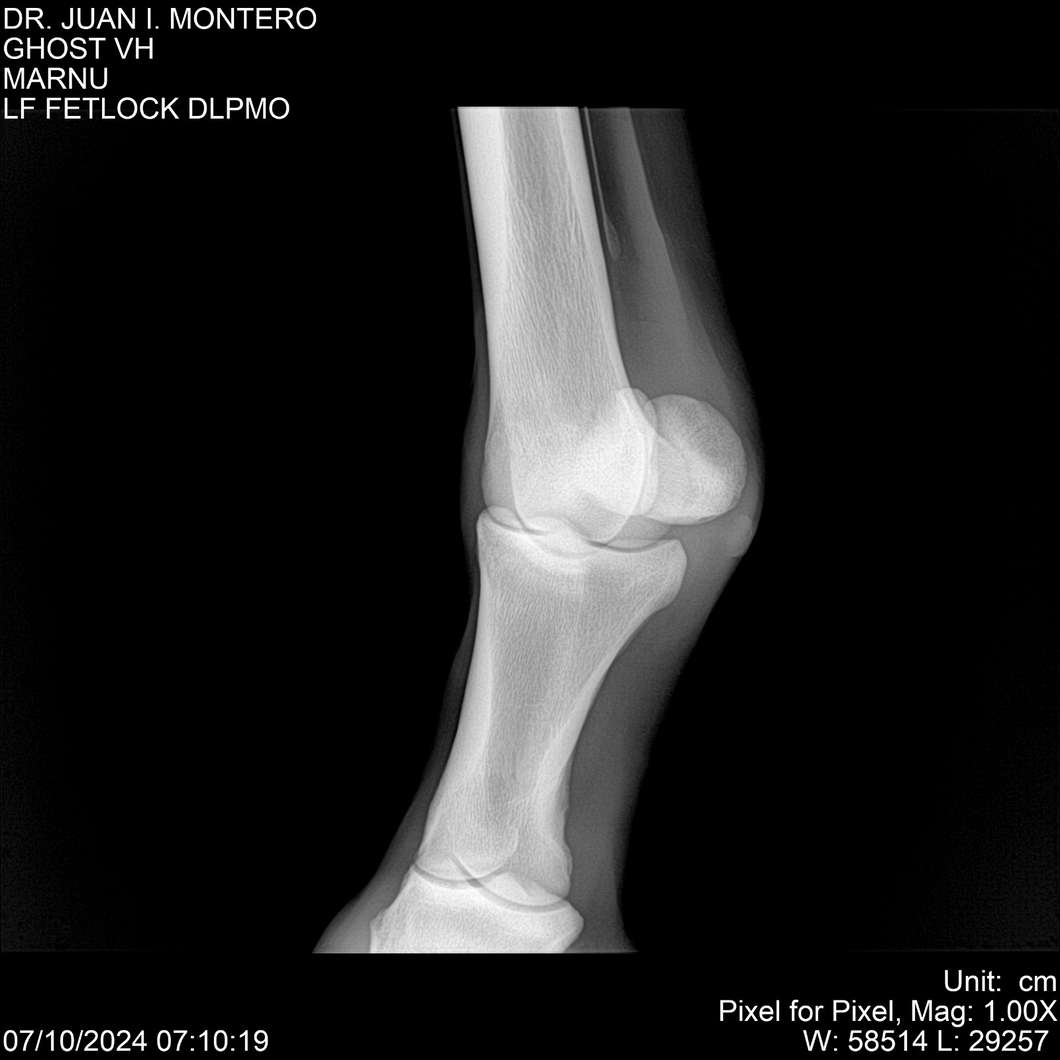

LOTE 15, GHOST VH 🔥 🔥 🔥 Lote Anterior Volver al remate Lote Siguiente Ficha Contacto Montevideo - Ficha del Lote Identificador: #282525 Categoría: Yeguarizos Montevideo - 69 Visualizaciones ClicData Contacto Empresa: Abelenda N. R., Walter Hugo Nombre*: Teléfono* : E-mail* : Mensaje Enviar Registrese gratis Este contenido Exclusivo está disponible sólo para usuarios registrados Ingresar